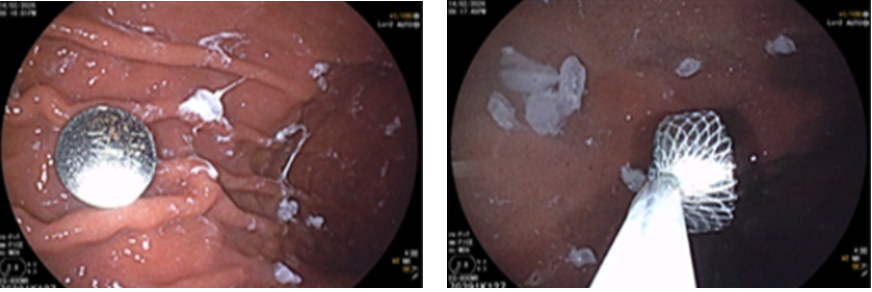

While family members were preparing and entertaining guests, 9-year-old V.Q.T (Hanoi) accidentally swallowed a button battery — the kind found in toys, remote controls, or decorative lights.

X-ray showing the button battery in the child’s stomach.

The family brought him for medical care promptly. An X-ray confirmed the object in his abdomen, and it was safely removed via endoscopy. However, button batteries can cause chemical burns within just a few hours, seriously damaging the throat or stomach if not handled quickly.